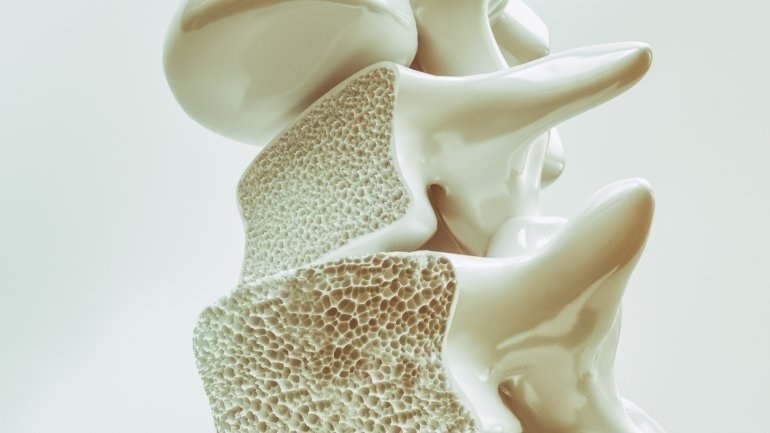

Ο περιορισμός βάδισης αυξάνει τον κίνδυνο κατάγματος

Ο περιορισμός στο περπάτημα σχετίζεται σημαντικά με τον κίνδυνο κατάγματος σε μια διάρκεια 4-5 ετών, σύμφωνα με μια μελέτη που δημοσιεύθηκε στο JAMA Network Open.